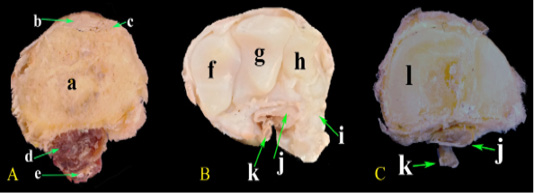

Photomacrograph of the cross sections at different levels of the carpal region. (A) At the distal extremity of radius, (B) At the middle carpal bones, (C) At the metacarpus. a-Radius; b- Extensor carpi radialis M.; c- Common digital extensor M.; d- Deep digital flexor M.; e- Superficial digital flexor M.; f- Radial carpal bone; g- Intermediate carpal bone; h- Ulnar carpal bone; i- Accessory carpal bone; j- Deep digital flexor tendon; k- Superficial digital flexor tendon; l- Metacarpal bones.